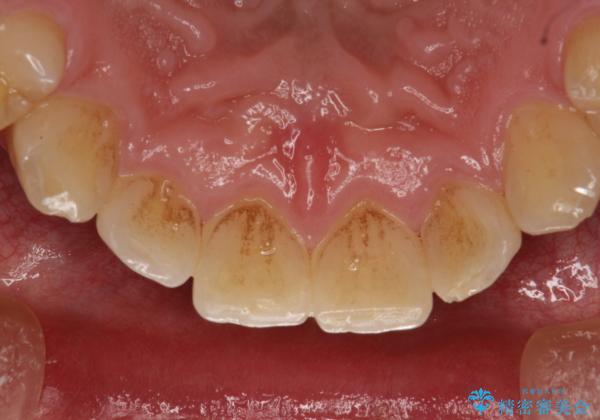

60分のPMTCで歯の黄ばみをきれいに除去

- 年末年始と忙しく、なかなか歯のケアがしっかりできなかった事と着色も気になるとのことで来院されました。PMTC60分コースを行いました。